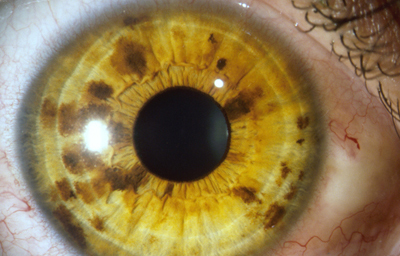

La Heterocromia Iridis y la Heterocromia Parcial o Sectorial

Son variantes, en la que un Iris es completamente diferente en color al Iris del otro ojo, o un Iris tiene un sector de diferente color a otro sector; es poco común y frecuentemente se asocia con enfermedades oculares, pero existen en los humanos como variantes normales.

El Color del Iris

El Iris en general es muy pigmentado con colores que comúnmente van del marrón, avellana, gris, verde y azul. Existen los iris sin pigmento en el Albinismo oculo-cutáneo en cuyo caso se ven blanco/rosados.

El color del Iris es un fenómeno complejo por efectos combinados por la textura, la pigmentación y el tejido fibrovascular del estroma, junto con la constitución epigenética del individuo. Desde el punto de vista óptico, la simple absorción o reflexión selectiva por algunas moléculas, como la hemoglobina o el colágeno del estroma que son componentes no pigmentados, puede tener influencia en el color que es observado.

A pesar de la gran variedad en el color del Iris, el único pigmento que contribuye en forma sustancial es la melanina; su cantidad, es uno de los factores que determina el color del iris en una persona. Estructuralmente el color depende de la cantidad variable de eumelanina (melaninas marron/negra) y pheomelanina (melaninas rojo/amarillo) producidas por los melanocitos derivados de la Cresta Neural. El grado de dispersión de la melanina que yace en racimos subcelulares en los melanosomas, tiene cierta influencia en el color que se observa, pero el grado de dispersión no es reversible ya que los melanosomas no son moviles.